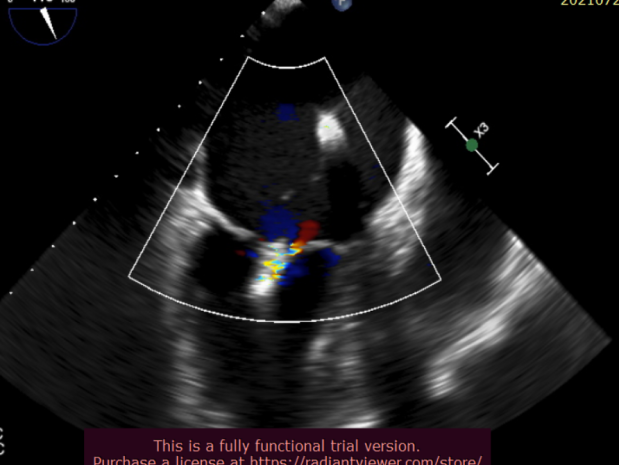

北部战区总医院心内科团队成功完成全新经股静脉缘对缘瓣膜修复系统 全国多中心临床研究首例植入手术